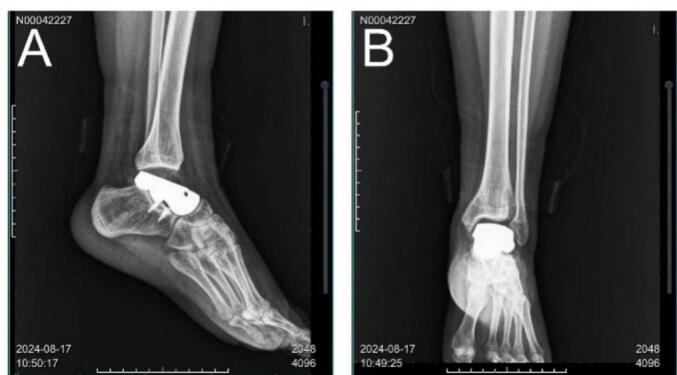

Physical examination revealed a palpable mass in front of the ankle, mild tenderness, normal skin temperature, palpable distal blood flow and sensation, and slightly restricted movement of the left ankle. By reviewing her medical history, we excluded trauma, surgical intervention, familial inheritance, infection, hormonal factors, and rheumatoid conditions. Preoperative ankle function was primarily characterized by limited dorsiflexion, with an AOFAS score (American Orthopedic Foot & Ankle Society) of 75 out of 100. X-ray and CT images of the ankle demonstrated osteolytic lesions of the talus, with marginal sclerosis not being prominent, local cortical discontinuity in front of the talus, and a reactive soft tissue mass (Fig. 1 A, B). Enhanced MRI of the ankle revealed slightly low signal intensity on T1-weighted imaging (T1WI) (Fig. 1 C, F), uneven high signal intensity on T2-weighted imaging (T2WI) and fat suppression sequences, uneven enhancement of the lesion, a soft tissue mass surrounding the talus, and significant edema with poorly defined boundaries (Fig. 1 D, E). The bone scan confirmed the absence of distant metastasis. To further clarify the diagnosis, a talus puncture biopsy was performed, and the pathological analysis indicated epithelioid hemangioendothelioma(Fig. 2).

Fig. 1.

Imaging findings at presentation. (A,B) preoperative X-ray Radiographs. The ankle showed osteolytic lesions of the talus, marginal sclerosis was not obvious, local cortical discontinuity in front of the talus, and reactive soft tissue mass was formed. Magnetic resonance imaging findings of the ankle (C, F) Enhanced T1-weighted images. Enhanced MRI of the ankle showed slightly low signal intensity on T1WI, uneven enhancement of the focus, soft tissue mass around the talus, obvious edema and unclear boundary. (D)T2-weighted images. Uneven high signal intensity on T2WI and fat suppression sequence. (E)T1-weighted images.